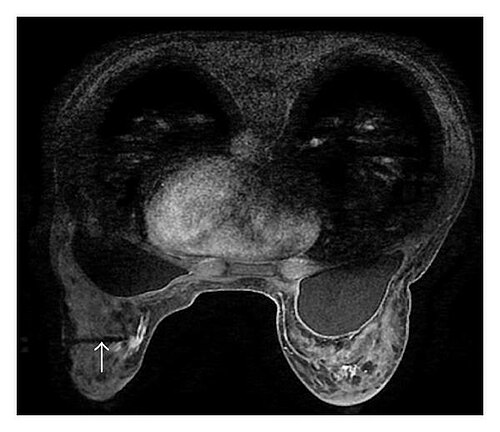

Normal knee phantom with intact bone, cartilage, menisci, and ligaments for baseline comparison

Knee with complete ACL rupture showing torn ligament, bone bruises on lateral femoral condyle and posterolateral...

Knee with medial meniscus tear (bucket-handle type) showing displaced meniscal fragment, joint effusion, and...

Degenerative knee with joint space narrowing, osteophytes, subchondral sclerosis, cartilage thinning, and Baker's cyst